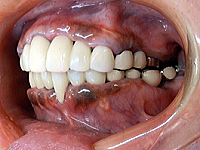

(写真3)治療中の写真 右側

初診時に、咬み合わせが不良のために起きていた顎関節症も、仮歯を早期に装着することにより解消されて、

大変楽になったとのことであった。